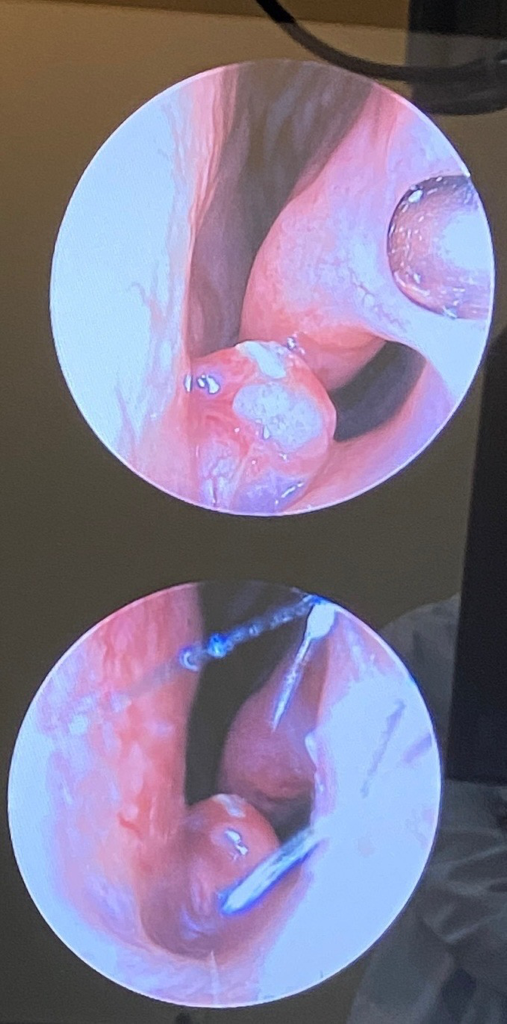

대부분의 비 용종의 경우, 특이 증상이 없는 경우, 수술을 권하지는 않지만

점차 커지거나 불편한 경우, 제거 수술을 하게 됩니다. 전신 마취가 필요한

수술이기 때문에 이비인후과 진료 후 결정하는 것이 필요합니다.